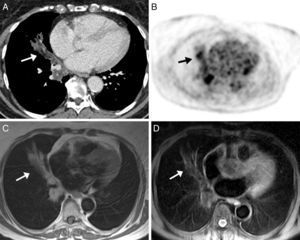

Dados los antecedentes oncológicos de la paciente, se decidió realizar una tomografía por emisión de positrones (PET)/TC. En el componente PET del estudio se observaron áreas hipermetabólicas en las zonas de consolidación pulmonar. En el componente de TC se objetivó la presencia de opacidades parenquimatosas con atenuación grasa, emitiéndose el diagnóstico de presunción de neumonía lipoidea. Debido a que la paciente rehusaba realizarse una fibrobroncoscopia, se optó por ampliar el estudio de la opacidad mediante RM de tórax, en la que se evidenciaron zonas hiperintensas en secuencias potenciadas en T1, que se suprimían en secuencias con supresión grasa (por ejemplo, la secuencia STIR) (fig. 2). Estos hallazgos eran compatibles con NLE.

Imagen axial de TC de tórax en ventana de mediastino (A) en la que se observa una opacidad en pulmón derecho de distribución peribronquial, con áreas de atenuación grasa (flecha). Imagen de PET (B) en la que se observan áreas hipermetabólicas en la base pulmonar derecha, coincidiendo con las opacidades visualizadas en TC (flecha). Imágenes axiales de RM, en la que se demuestra hiperintensidad de señal de la opacidad en secuencias potenciadas en T1 (C) y supresión de su señal en secuencia de saturación grasa (D) (flechas).

Tras suspender el uso de vaselina para el cuidado de la cánula de traqueotomía y administrar corticoides a dosis bajas, se constató resolución radiográfica completa (6 meses) de la opacidad.